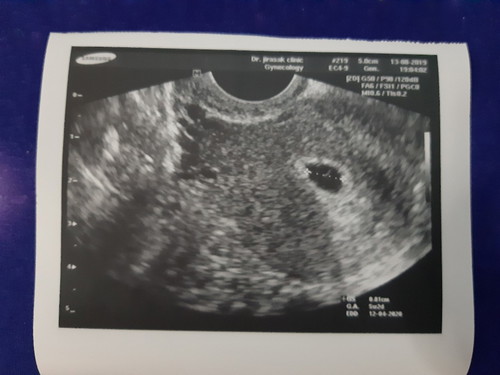

สวัสดีแม่ๆทุกๆคนนะคะ เมื่อเดือนที่แล้วไปตรวจมะเร็งปากมดลูกมาผลค่ามะเร็งผิดปกติคุณหมอนัดส่องกล้องวันที่15ส.ค.นี้ แล้วดันคัดหน้าอก แล้วรู้สึกผิดปกติกับร่างกาย เลยทำงานตรวจครรภ์เมื่อวานปรากฎว่าน้องมาจ้า วันนี้ได้ไปหาคุณหมอที่คลีนิคมาก็รู้สึกโล่งใจ ขึ้นมานิดหน่อย ตอนนี้อายุครรภ์ 5Week 2 Day มีใครเจอเหตุการณ์แบบนี้บ้างไหมคะ??